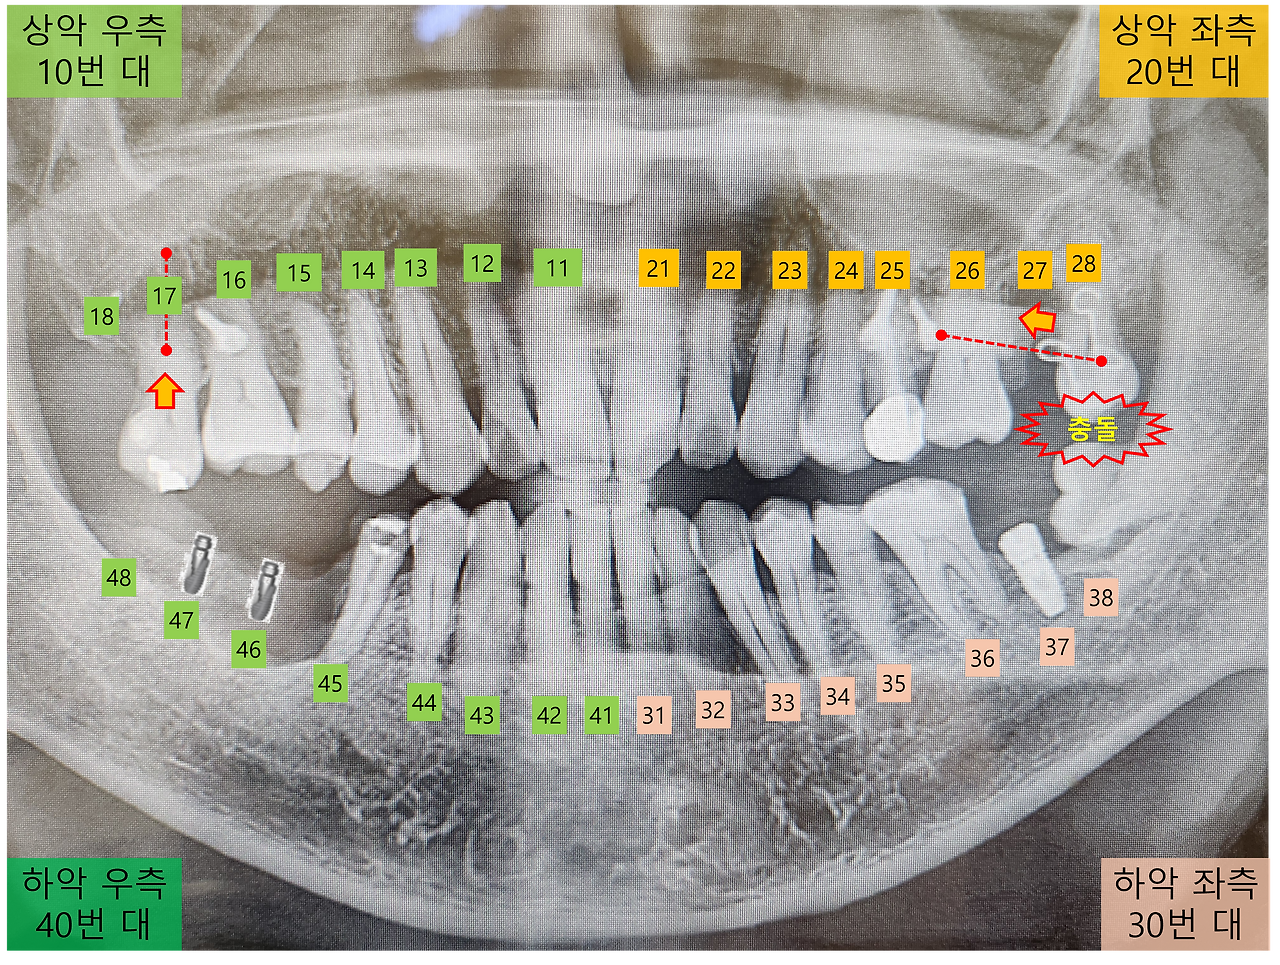

지난번 교정 장치에 대한 점검 시, 28번 치아가 아래쪽 사랑니와 부딪치는 현상이 있어 약간 갈아내는 치료가 있었습니다. 이때부터 일주일간은 아무런 불편 없이 편하게 식사를 할 수 있었습니다.

왼쪽 치아 충돌.png

그런데 최근 28번 치아에 불편함이 느껴지기 시작했습니다.

아무래도 또다시 사랑니와 맞닿는 것이라 생각되네요.

제가 봐도 28번 치아와 부딪칠 수 있는 것은 옆으로 누워있는 사랑니 외에는 없으니까요.

자꾸 사랑니와 부딪치다보니, 입을 가만히 다물고 있을 때도 28번 치아가 잇몸에서 들뜬 듯한 느낌이 듭니다.

음식을 씹을 때는 그나마 치아 사이에 음식물이 있어 불편함이 덜 하지만, 입을 꽉 다물면 다른 치아보다 먼저 닿으며 어긋나는 불편한 느낌이 있습니다.

이런 상태가 이틀 정도 지속되면서, 음식물을 씹다가 갑작스러운 통증에 깜짝 놀라는 순간도 있었습니다.

원래라면 바로 치과에 가서 상태를 확인하고 치료를 받아야 하는데, 이번에는 좀 더 견뎌볼까 하는 생각이 듭니다. 아무래도 교정 장치로 인해 치아가 조금씩 이동하면서, 자리가 잡히면 증상이 나아질 것 같아서입니다.

다행히 사흘째가 되자 통증은 사라지고, 음식물을 씹는데 큰 불편함이 없습니다.

다만 치아가 어긋나면서 발생하는 "뿌드득" 소리와 그 느낌은 여전히 신경을 자극합니다.